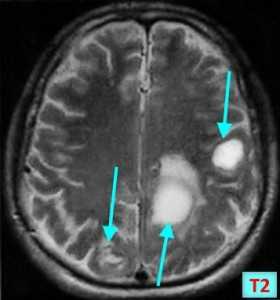

МРТ-признаки метастазов в мозг

МРТ — более чувствительный и специфичный метод в выявлении метастазов ЦНС по сравнению с компьютерной томографией. Вторичные опухоли имеют ряд общих черт при МР-исследовании.

Т2 ВИ

- Гиперинтенсивный сигнал от центрального участка метастаза

- Повышение интенсивности сигнала от отечных тканей мозга, окружающих вторичную опухоль, вследствие чего метастазы становятся более четкими на изображениях

МРТ с контрастным усилением

- Выраженное увеличение интенсивности сигнала

- Усиление сигнала по периферии в виде «кольца» или «короны»

Метастазы головного мозга на МРТ. Фото. Определяются множественные метастазы в мозг при раке легкого: слева в режиме Т1-ВИ в виде гипоинтенсивных образований, справа — в режиме Т2-ВИ виде множественных участков повышенного сигнала, окруженных зоной перифокального отека. У пациента подтверждена первичная опухоль легкого.

Отдельно необходимо рассмотреть МР-признаки метастазов меланомы в головной мозг, которые обладают сигнальными характеристиками, отличающимися от других опухолей вследствие наличия меланина в структуре. Метастазы безамилоидной меланомы выглядят на МРТ аналогично метастазам других опухолей, описанным выше. На Т1-ВИ они имеют резко гиперинтенсивный (высокий, яркий) сигнал, а наТ2-ВИ — изо- либо гипоинтенсивный (пониженный) сигнал.